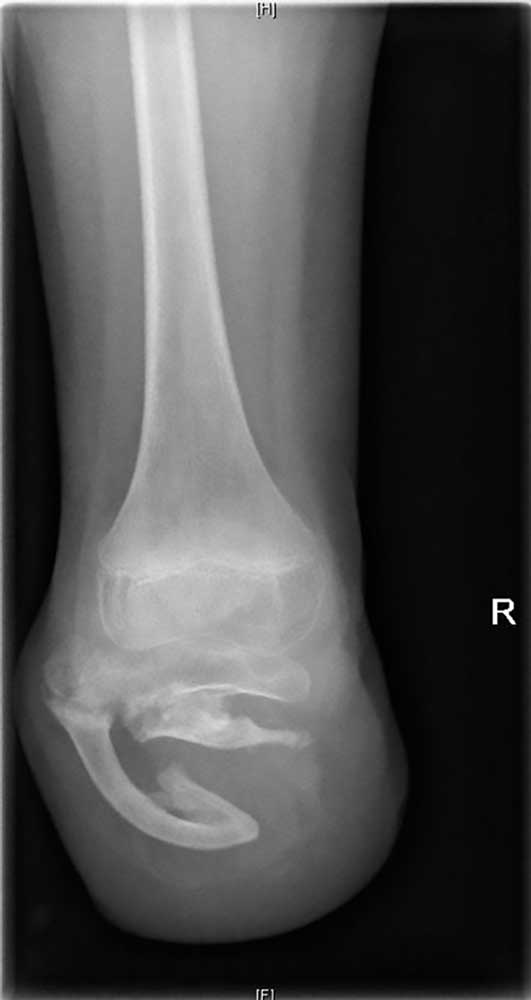

Es handelt sich um ein 9‑jähriges Mädchen, dem im Rahmen einer Streptokokkensepsis im Alter von 4 Jahren beidseitig die Unterschenkel amputiert wurden. Durch die frühe Amputation entstand eine sehr kurze Tibia, die sich im weiteren Verlauf jedoch nicht weiterentwickelte. Erfreulicherweise hat sich aber die Fibula durch die besondere Belastung und den „Prothesendruck“ der Tibia quasi unterstellt (Abb. 2). Somit ist nicht nur eine ausreichende Stumpflänge zur Prothesenversorgung, sondern auch eine ausreichende Stabilität gegeben, wodurch das Kniegelenk funktionell erhalten bleibt. Zwar müssen dabei aufgrund der sehr kurzen und eigentümlichen Hebelverhältnisse bestimmte Einschränkungen hinsichtlich der Kraftübertragung zwischen Stumpf und Schaft in Kauf genommen werden, und die Bettung des Stumpfes erfordert besondere Modelltechniken, die nicht analog zu einem klassischen Stumpf sind, aber es ergeben sich doch gute funktionelle Ergebnisse. Dennoch bedarf es einer engen Anbindung an das Versorgungsteam und einer engmaschigen Kontrolle der Patientin im weiteren Verlauf, um potenziell negativen Entwicklungen rechtzeitig begegnen zu können.